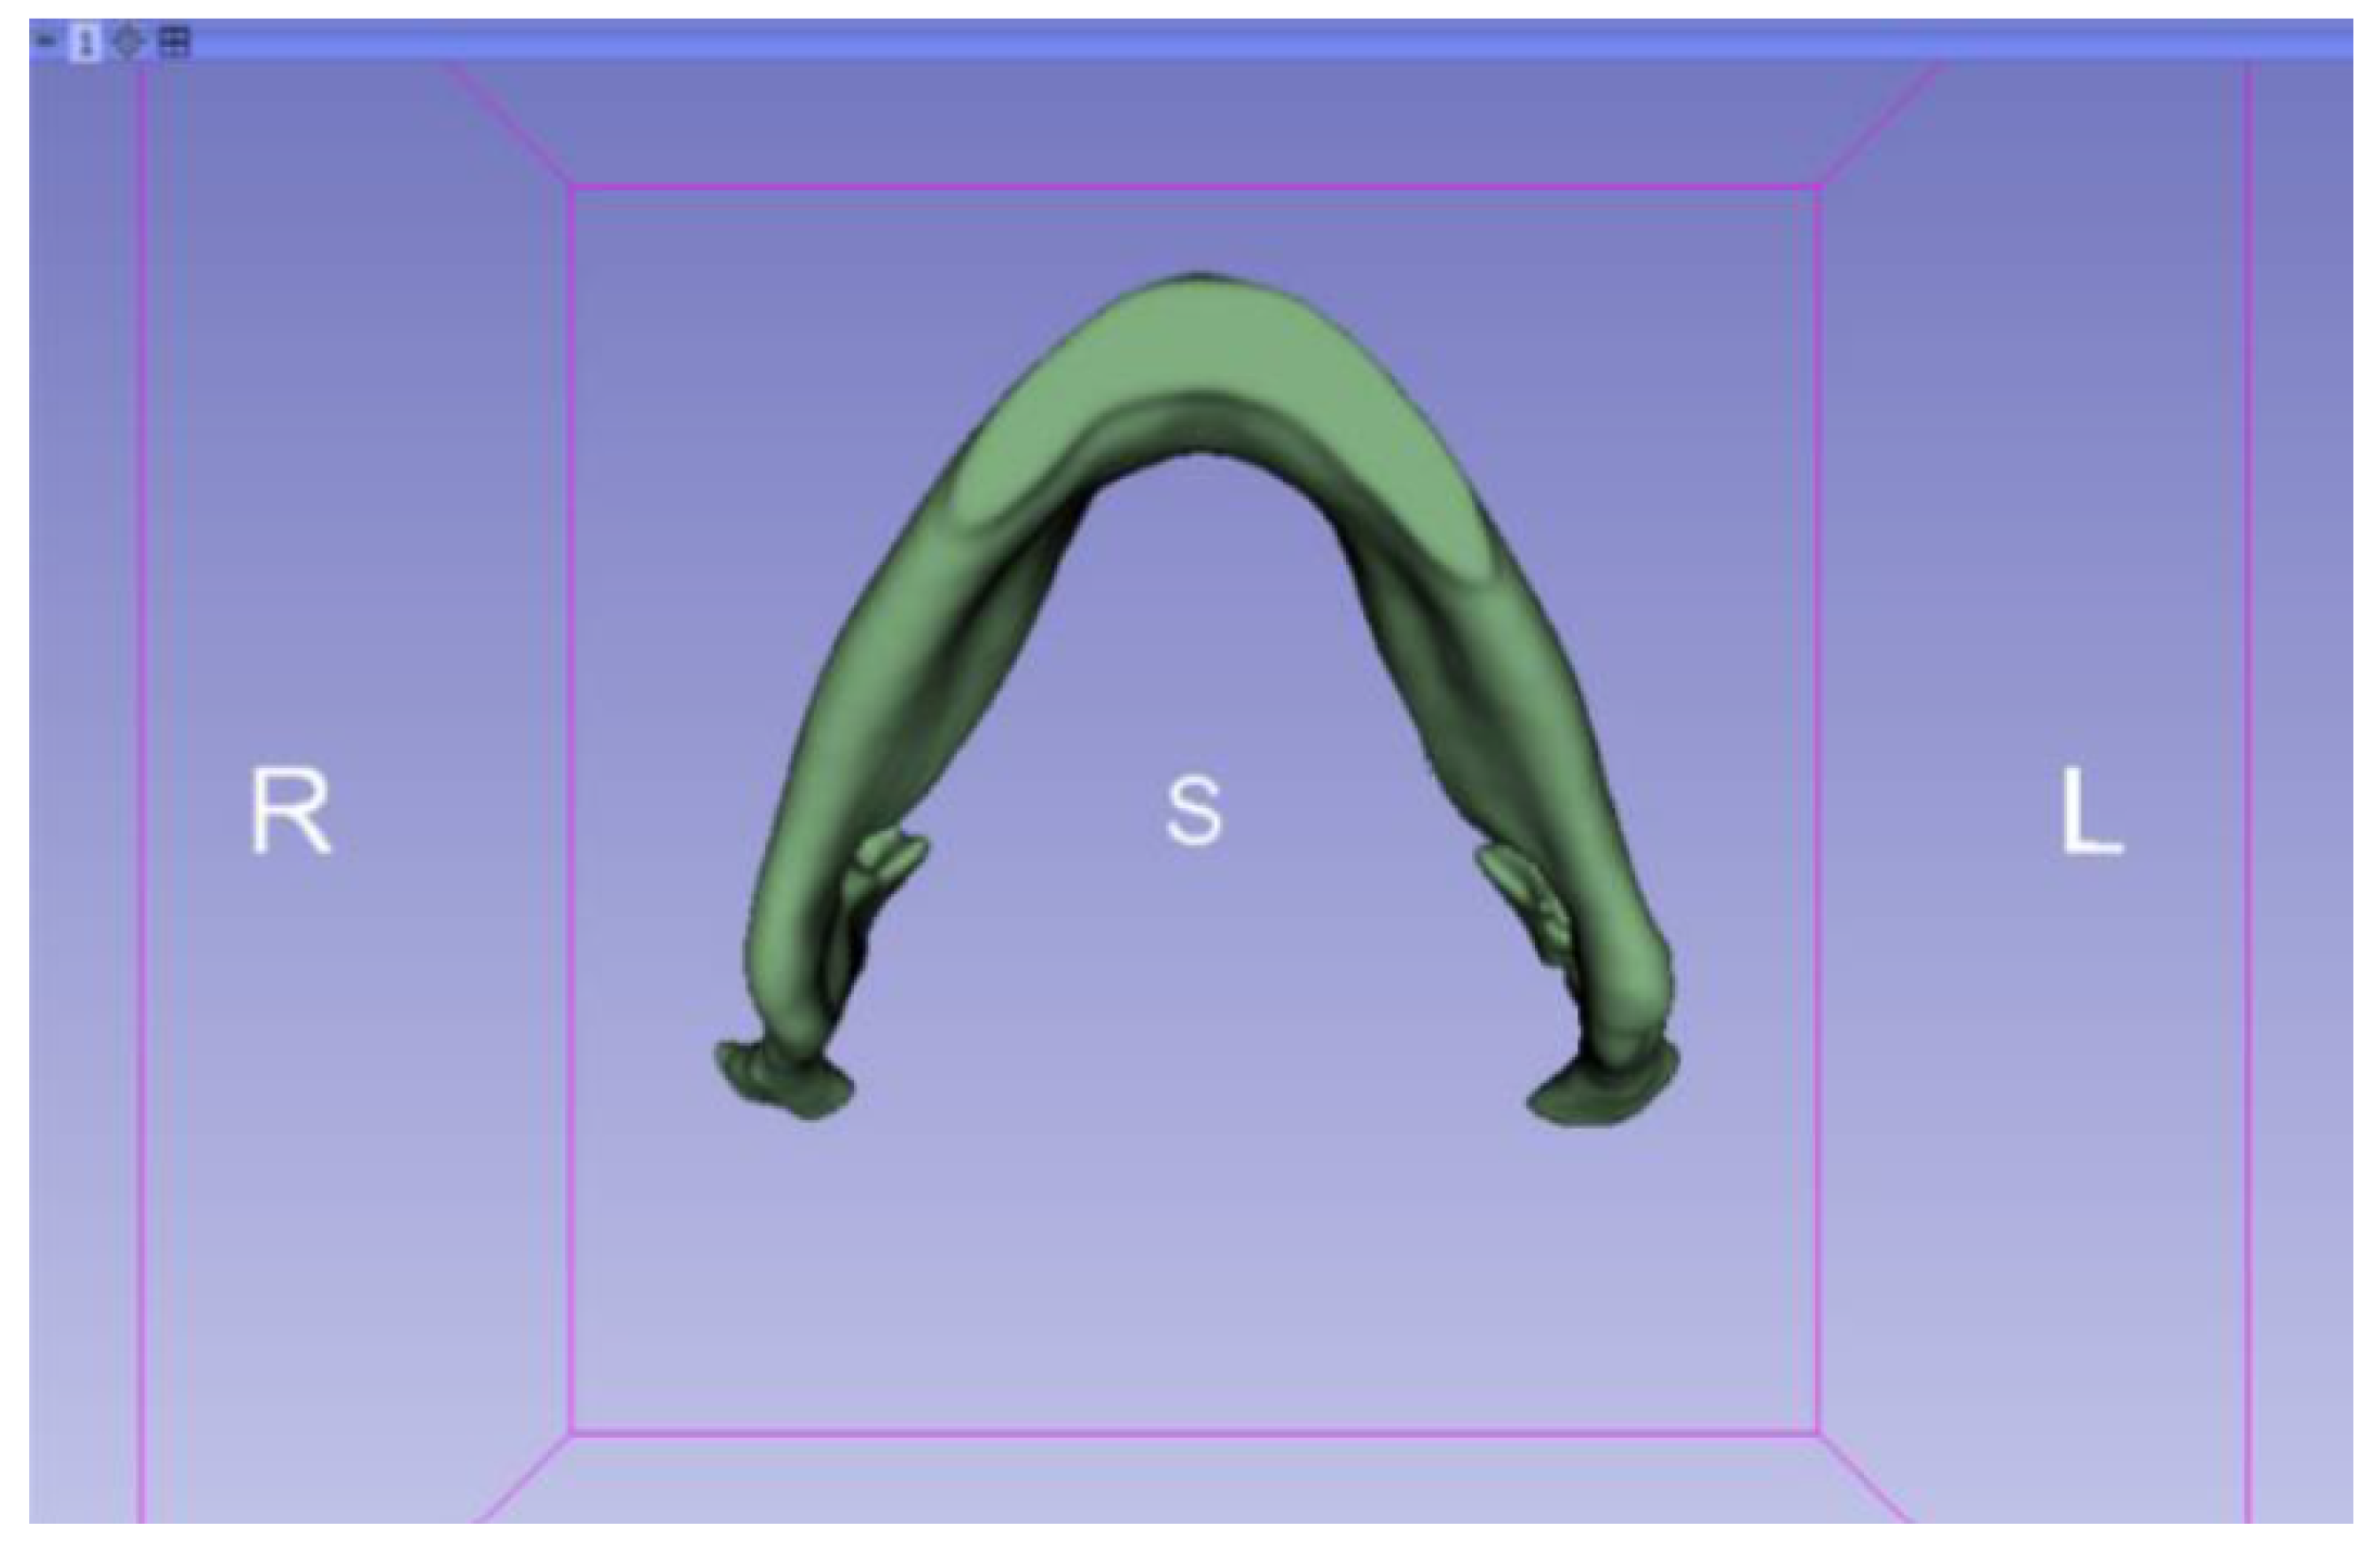

3.2. Human Lower Jaw

3.2.1. DICOM-to-STL Files